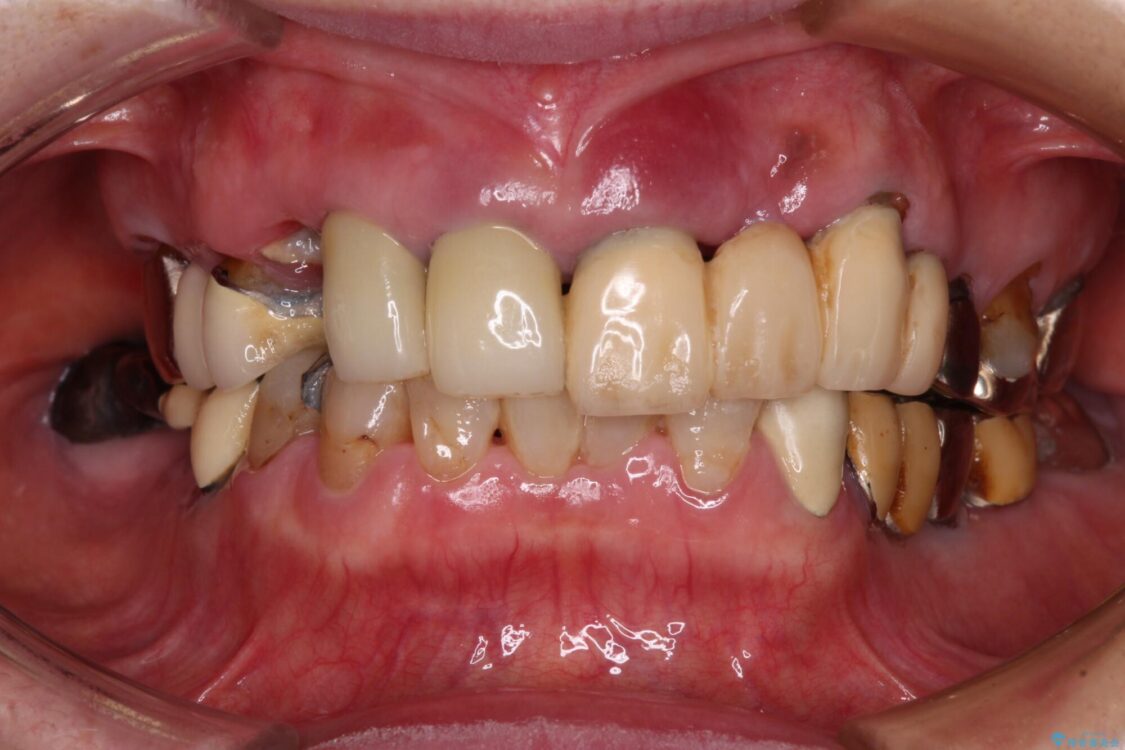

治療前

• 後戻りでデコボコの前歯 インビザライン矯正治療 治療前画像